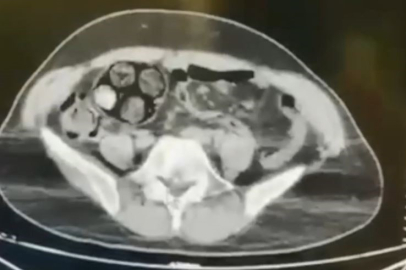

Edinilen bilgiye göre, Artvin İl Jandarma KOM Şube Müdürlüğü ekipleri, İran uyruklu Farshid Rafıeıeınsheykh (43) adlı şüphelinin 8 Mart tarihinde vücudu içerisine uyuşturucu madde gizleyerek Artvin’e getireceği bilgisi üzerine çalışma başlattı. Yapılan takip sonucu Artvin merkez Çayağzı Mahallesi’nde yakalanan şüphelinin üst aramasında herhangi bir suç unsuruna rastlanmadı. Bunun üzerine şüpheli, Ceza Muhakemesi Kanunu'nun 75. maddesi gereği iç ve dış beden muayenesi için Artvin Devlet Hastanesine sevk edildi. Çekilen tomografi sonucu zanlının bağırsaklarında 10 paket tespit edildi. Cerrahi müdahale ile çıkarılan paketlerin içinde toplamda 350 gram metamfetamin maddesi olduğu belirlendi. Gözaltına alınan İranlı zanlı hastanede müşahede altına alınırken, olayla ilgili soruşturma başlatıldı.

Zanlının hastaneden taburcu olmasının ardından hakim karşısına çıkarılacağı bildirildi.